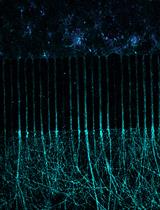

The cisplatin drug toxicity result for MDA-MB-231 cells is shown in Figure 7.

Figure 7. The Cisplatin (Cis) drug toxicity test on MDA-MB-231 breast cancer cells. A. The on-chip fluorescence image results for 0 μM, 10 μM Cis-treated MDA-MB-231 cells for 24 h. B. The drug toxicity test results for Cis-treated MDA-MB-231 cells on /off-chip (96-well plate).